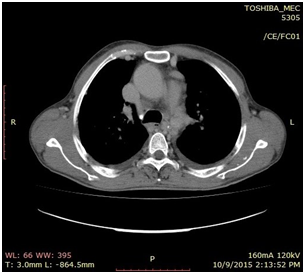

A 35year-old male patient was referred to our interventional radiology clinic by a cardiothoracic surgeon with a diagnosis of possible coarctation of the aorta with concurrent severe aortic stenosis. His primary complaint was severe shortness of breath and lower extremity weakness with minimal exertion. His symptoms had been progressively worsening and at presentation he could barely walk a distance of 15meters before stopping to rest. On physical examination, he had bounding bilateral radial pulses with faintly palpable femoral pulses. A CT angiogram of the chest was ordered which demonstrated a severe focal stenosis of the descending thoracic aorta, 2cm distal to the takeoff of the left subclavian artery. The aorta measured 18mm proximal to the stenosis and 20mm distally. The proximal left subclavian artery measured 18mm. Normal great vessel branching anatomy was noted. The distal thoracic/abdominal aorta, as well as the iliac and femoral vessels were widely patent with no evidence for atherosclerotic disease. Left ventricular hypertrophy was also noted on the CT scan. Given the history of severe aortic stenosis an echocardiogram was performed which demonstrated mild concentric left ventricular hypertrophy. A thickened and calcified aortic valve was noted with severe aortic stenosis and an aortic valve peak gradient of 100mmHg. The estimated pulmonary artery systolic pressure was 73mmHg. Given the constellation of findings on the chest CTA, and after consultation with the referring thoracic surgeon, a decision was made to proceed with catheter angiography with a plan to treat via an endovascular approach. The surgeon would then repair the aortic valve once the coarctation had been treated.

Figure 1 CT Angiogram demonstrating a severe focal stenosis of the descending thoracic aorta 2 cm distal to the takeoff of the left subclavian artery.